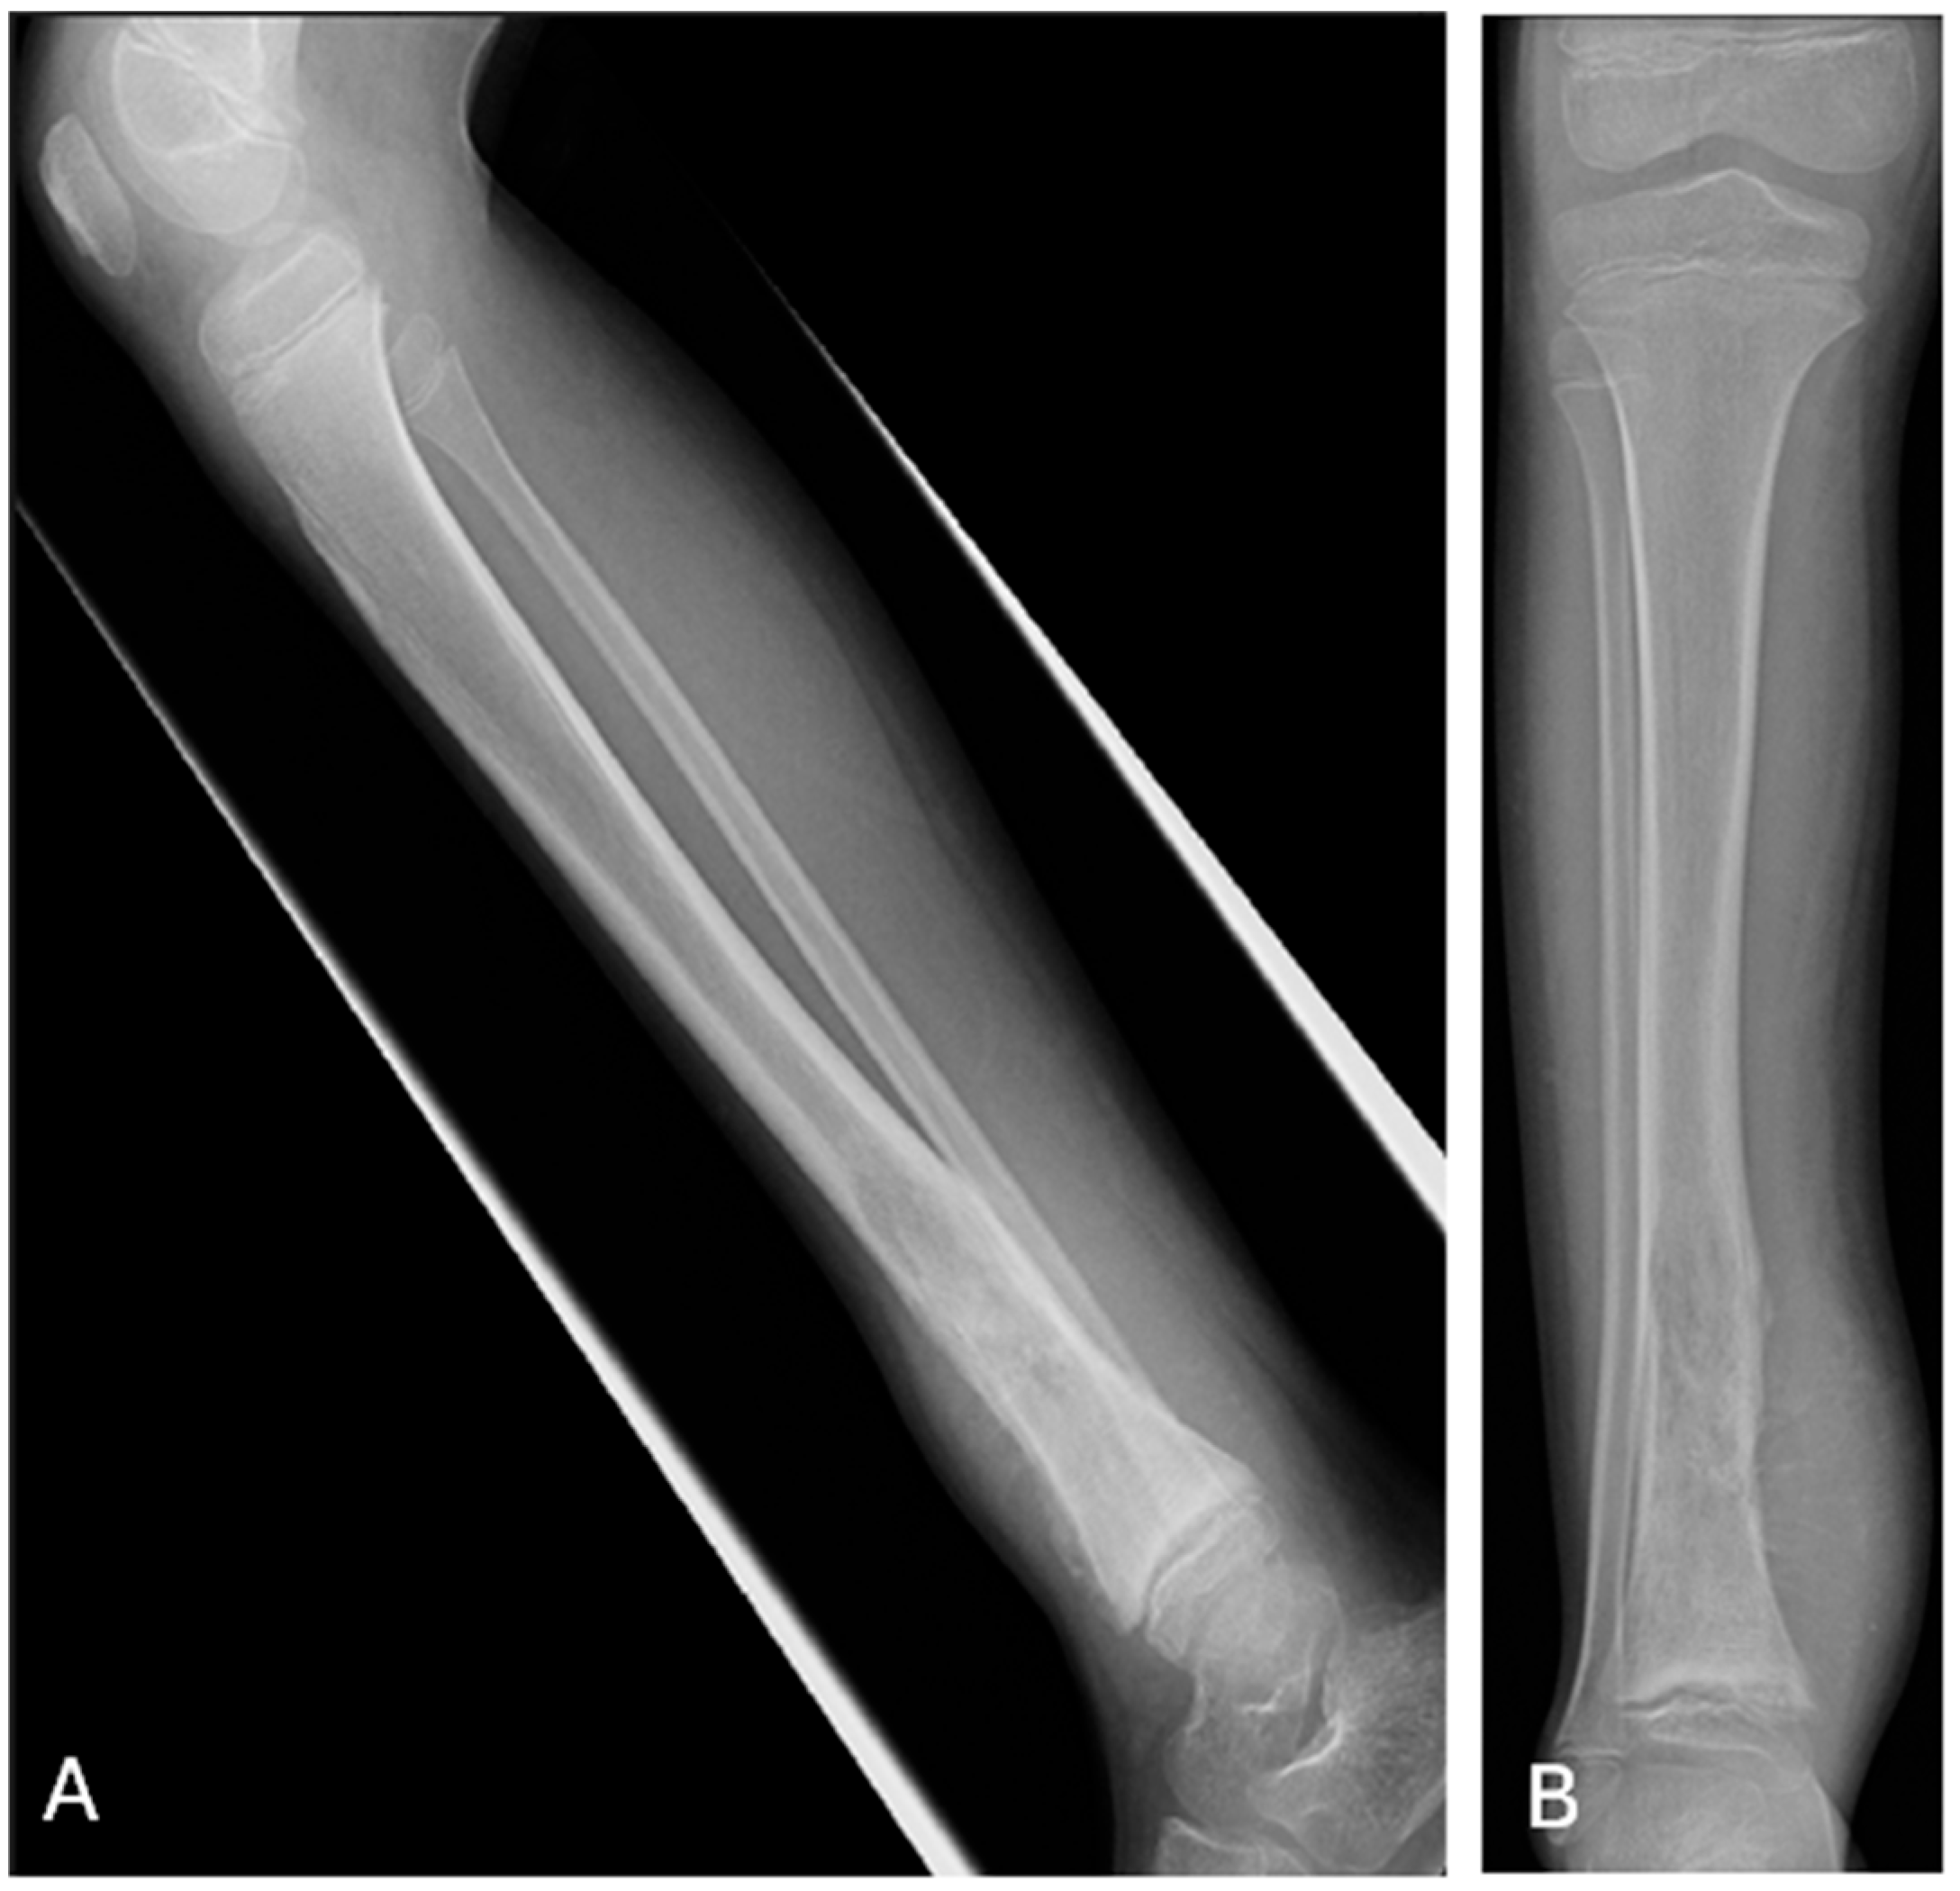

Each of the steps along this logical reasoning pathway can provide evidence for residents’ achievement of milestones and EPA fulfillment, from the Transition to Discipline (TTD) phase through to the Transition to Practice (TTP), and can be assessed in a resident’s adequately structured report [7]. Evaluation and grading (awarding of points) of each step along the path can be utilized to provide a more standardized assessment of residents and better allow comparison with peers and overall progression through residency, as illustrated with the following case (Figure 1) and the associated senior and junior residents’ reports (Figure 2 and Figure 3).

Figure 1. Radiographs of the tibia provided for sample case of aggressive osseous tibial lesion including (A) frontal and (B) lateral projections.

Step 1—Initially, the resident is evaluated on recognizing the abnormality. This can be determined from the resident’s report, including their PACS note. At the beginning of residency, this will be heavily weighted towards ER (on-call) exposure and common conditions (e.g., pneumothorax). We expect the resident, early on, to recognize an obvious or emergent finding, in order to show competence for on-call duties. The perception of the abnormality can be allocated points in the grading of the report (i.e., 3 points for identification of the primary abnormality versus 0 points for missing it).

Step 2—After evaluating the resident’s ability to perceive the abnormality, we can grade how the resident described the abnormal finding. We expect the senior’s description to be more precise and to utilize standard jargon, compared to the junior’s. This allows for variability in point allocation and provides a means to stratify residents’ abilities (i.e., 3 points for a description of an aggressive ill-marginated mixed lytic and sclerotic tibial metaphyseal lesion versus 1 point for a description of a tibial radiolucency).

Step 3—After perception and description of the primary abnormality, we can then grade the identification and description of the associated positive findings (i.e., 2 points for a description of an interrupted periosteal reaction and another 2 points for an associated soft tissue mass, as in this case).

Step 4—Knowing and reporting the significant associated negative findings provides evidence of an expanded knowledge base and further resident advancement (i.e., 2 points for a description of no involvement of the epiphysis and joint space and another 2 points for stating that there is no further lesion in the tibia).

Step 5—Further confidence and understanding of the positive and negative findings by the resident is reflected in the impression stating the suspected diagnosis and differential diagnoses, with points awarded or potentially subtracted. It would be expected that the senior’s report includes a more thorough differential and/or accurate diagnosis, as compared to the junior’s.

Step 6—Recommending appropriate follow up imaging and how it should be performed should be part of the standardized report and can be awarded points (i.e., in this case, 2 points for a recommendation of follow up MR to include both proximal and distal joints).

Step 7—Finally, the advanced resident report should include a recommendation for appropriate consultative services and with what urgency (i.e., in this case, 2 points for a recommendation of urgent oncologic and orthopedic consultations).